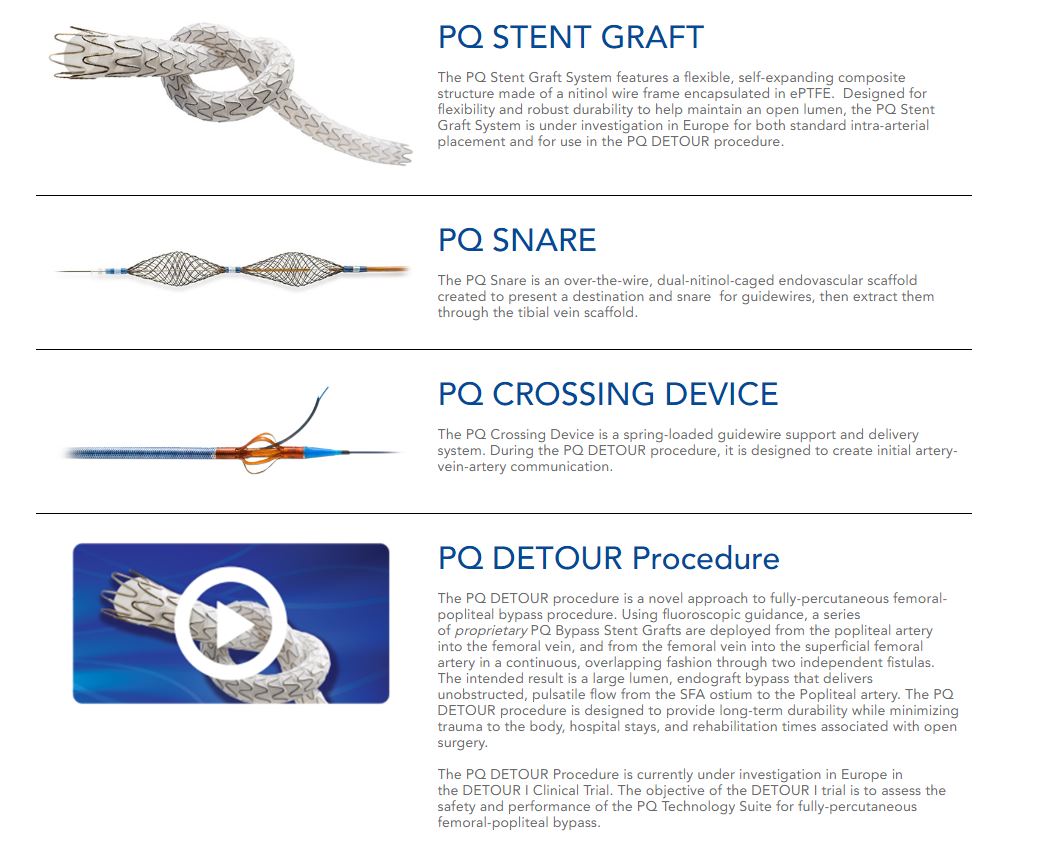

PQ Bypass gets FDA breakthrough device status for Detour System

PQ Bypass Announces CE Mark for DETOUR Percutaneous Bypass Technologies

PQ Bypass study meets safety efficacy endpoints MassDevice

PQ Bypass Incorporated docx 1 PQ Bypass Incorporated Performance

PQ Bypass Receives FDA Breakthrough Device Designation for the World

PQ Bypass Receives FDA Breakthrough Device Designation for the World

PQ Bypass Announces 60 Million Financing to Advance New Therapeutic

PQ Bypass Earns Frost amp Sullivan s European Technology Innovation Award

PQ Bypass Announces New President And CEO Medical Product Outsourcing

PQ Bypass Announces 60 Million Financing to Advance New Therapeutic